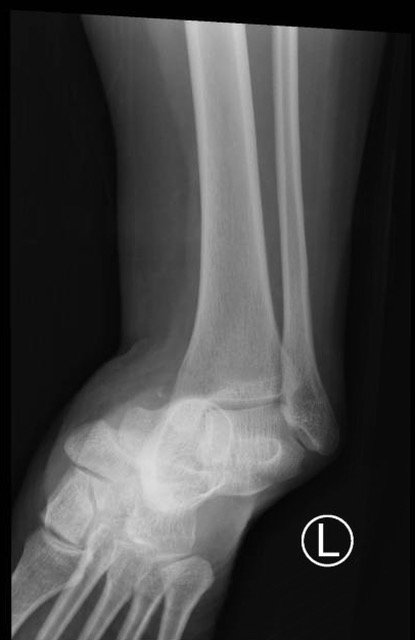

The X-rays were significant for a subtalar dislocation. The calcaneus (red) is laterally displaced with respect to the talar head (orange), and the white lines indicate the normal articular surface. Additionally, there was a talonavicular dislocation, as seen in the fourth image: the talus (green) and navicular bone (purple) overlapping suggests a dislocation. In a normally aligned foot, the boundaries of the two bones create a point of articulation.